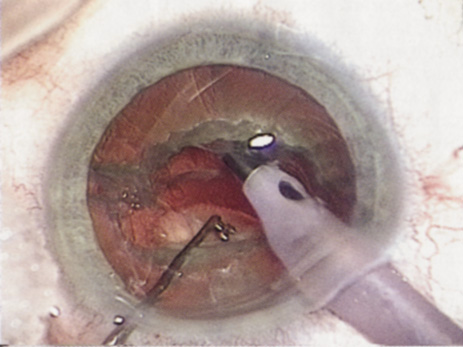

Many patients are most bothered by cataract-induced glare. For these patients, acuity testing under glare situations is indicated. There are several methods to assess visual acuity reduction by glare. The choice of method is often best dictated by the patient's history. If a patient complains of glare problems in the supermarket, or other uniformly illuminated environment, the brightness acuity test can be performed (Mentor Ophthalmics). For this test, the specially illuminated handpiece is held in front of the tested eye using best spectacle correction (Fig. 1). The Snellen acuity is rechecked and can be recorded on each of three light settings.